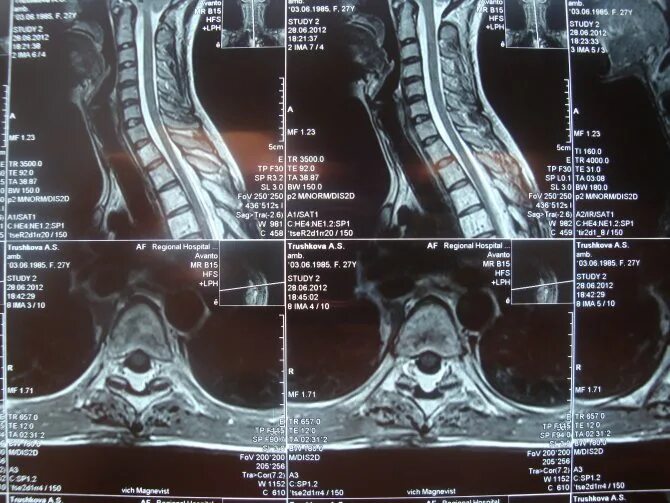

Перед мрт позвоночника можно кушать